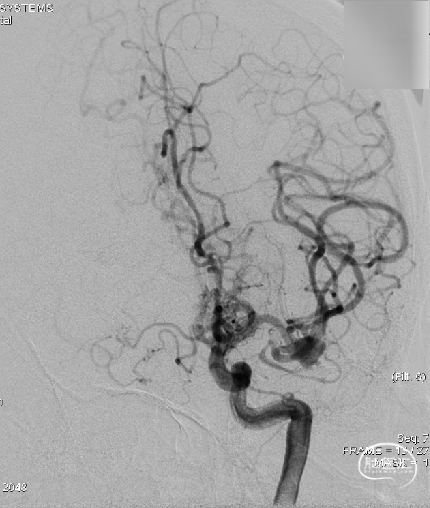

术前影像:术前正侧位。

术前影像:术前工作位。

三维重建:显示左侧MCA分叉部未破裂动脉瘤,约8.2mm*8.6mmm,瘤颈3.8mm,顶端有子瘤。